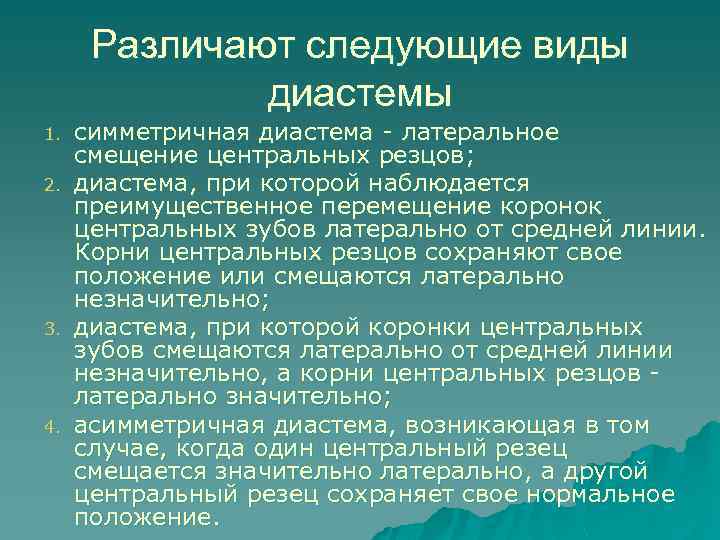

Различают следующие виды диастемы 1. 2. 3. 4. симметричная диастема - латеральное смещение центральных резцов; диастема, при которой наблюдается преимущественное перемещение коронок центральных зубов латерально от средней линии. Корни центральных резцов сохраняют свое положение или смещаются латерально незначительно; диастема, при которой коронки центральных зубов смещаются латерально от средней линии незначительно, а корни центральных резцов латерально значительно; асимметричная диастема, возникaющaя в том случае, когда один центральный резец смещается значительно латерально, а другой центральный резец сохраняет свое нормальное положение.